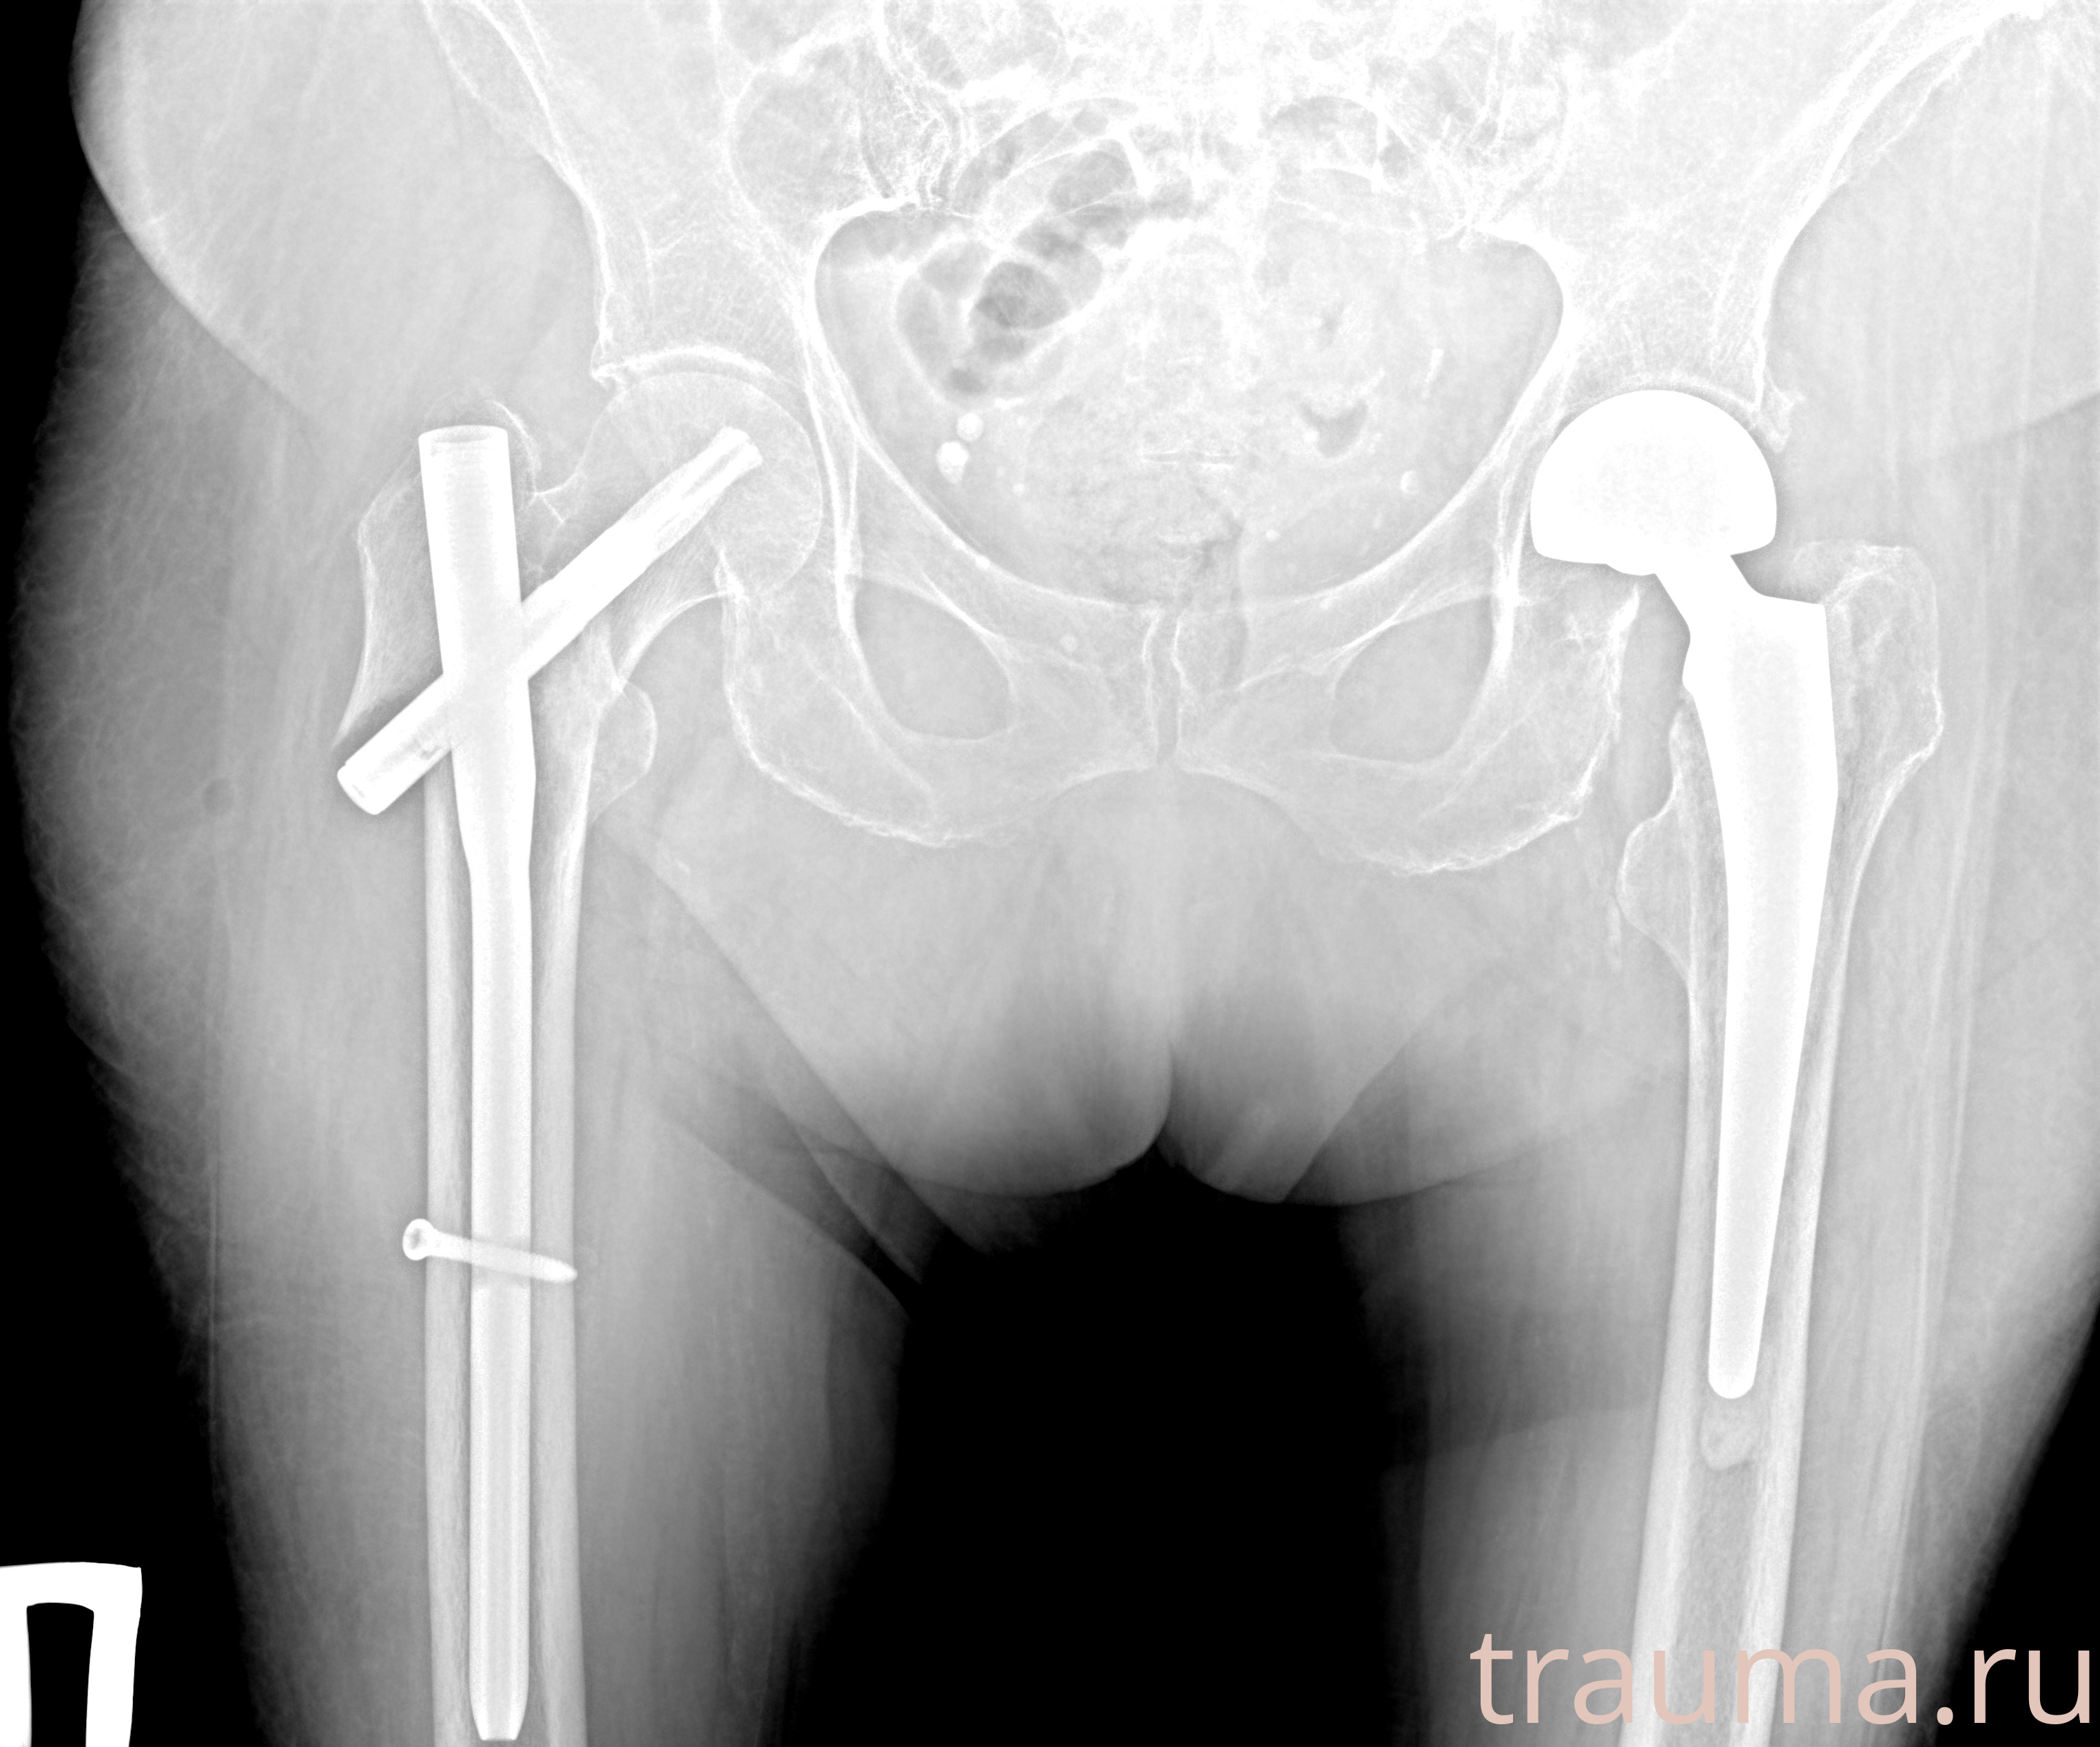

Рентген на дому: по вашему адресу приезжает врач-рентгенолог, травматолог-ортопед с мобильным рентгеновским аппаратом, проводит диагностику травмы или заболевания, делает необходимые рентгенограммы, дает рекомендации по дальнейшему лечению. Получить качественные снимки в домашних условиях возможно благодаря уникальной методике, разработанной МосРентген Центром для института  Склифосовского